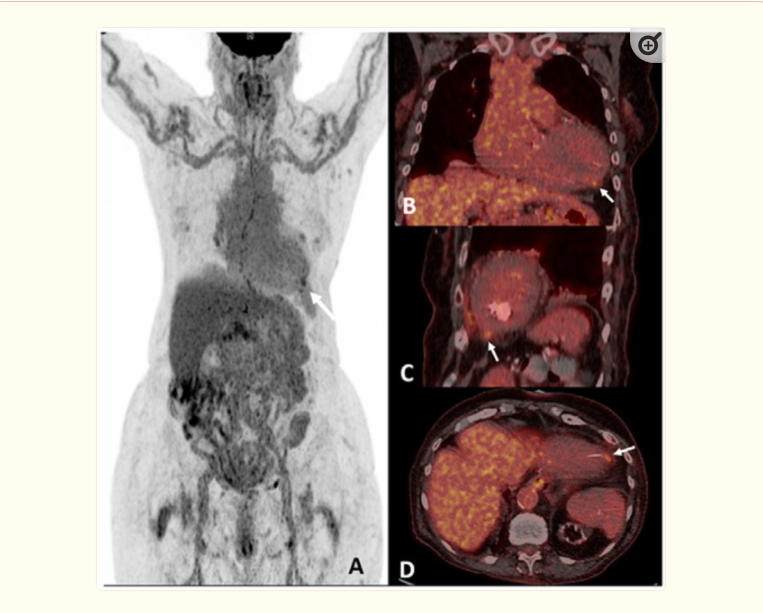

We report a 55-year-old male who received three doses of the Pfizer–BioNTech COVID-19 mRNA vaccine and subsequently developed progressive multi-organ dysfunction consistent with post-COVID-19 vaccine syndrome (PCVS), involving cardiopulmonary, neurologic, musculoskeletal, gastrointestinal, autonomic, otolaryngologic, audiovestibular, immune, ophthalmic, dermatologic, and psychiatric domains. Clinical manifestations included: pulmonary emboli; delayed MRI-confirmed myocarditis; neurocognitive impairment; small fiber neuropathy; autonomic dysfunction; myalgia; chronic pancreatic and gastrointestinal involvement; worsened tinnitus with sensorineural hearing loss; voice dysphagia and dysphonia; ophthalmic disturbances; chronic dermatologic inflammation; and anxiety/depression. The case was evaluated through a uniquely extensive longitudinal, multi-domain clinical investigation spanning molecular, immunologic, genetic, proteomic, transcriptomic, and tissue-based analyses, undertaken to characterize disease mechanisms and exclude alternative etiologies.

After >40 emergency department visits and >200 outpatient specialty encounters, the patient underwent >100 non-routine laboratory investigations and >100 imaging/functional studies. This evaluation systematically excluded underlying etiologic mechanisms across infectious, autoimmune, rheumatologic, endocrine, genetic, hematologic, malignant, toxic/medication-related, cardiovascular/vascular, metabolic, and primary neurologic domains. Testing remained largely nondiagnostic. A possible undocumented/undiagnosed asymptomatic infection manifesting as Long COVID was suspected after myocarditis diagnosis, and serology was pursued; unexpected results prompted expanded immune and tissue-based testing for spike- and vaccine-derived components. SARS-CoV-2 nucleocapsid antibodies were negative across five separate time points spanning 809–1,433 days post-vaccination, confirmed by three independent laboratories. The patient remains nucleocapsid negative with persistently elevated spike antibody levels (4,553 U/mL) 1,433 days after the final vaccination.